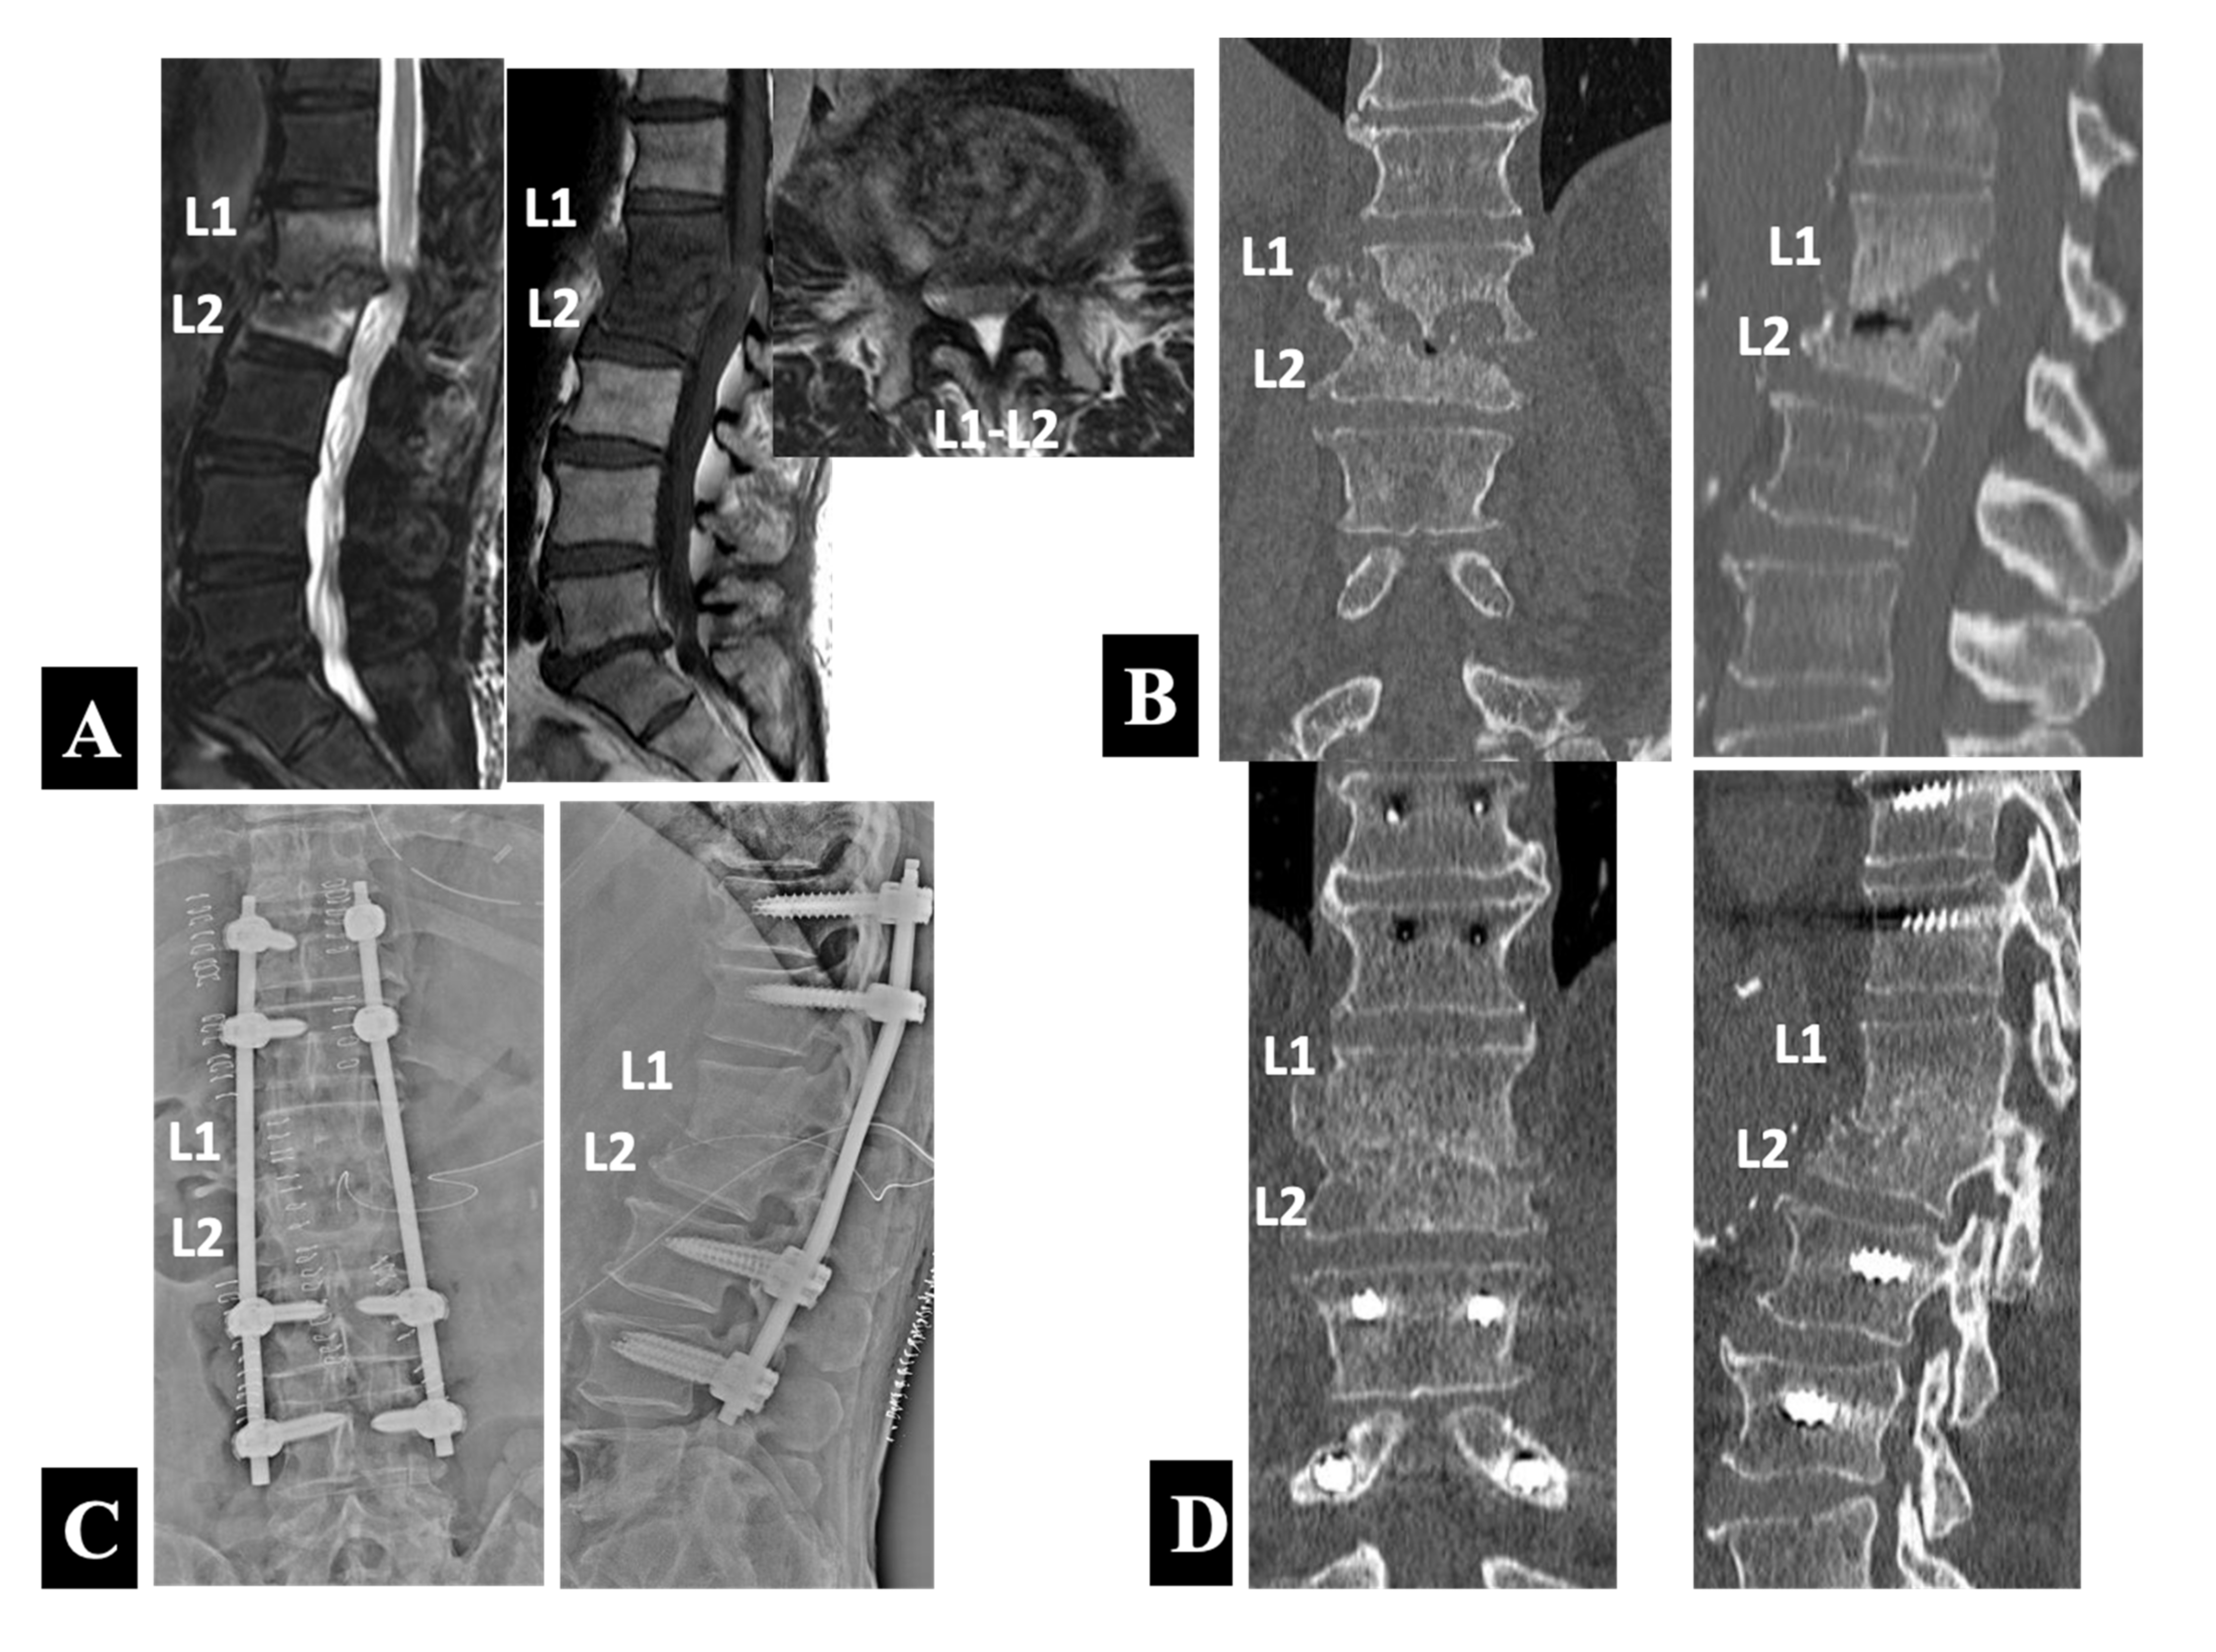

- Case 2 in Group 2-A (Figure 4):